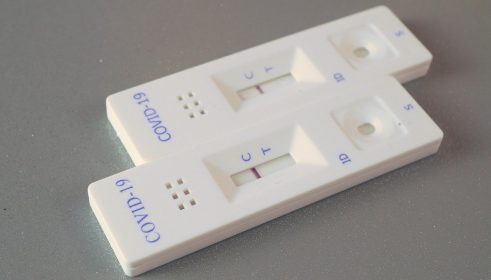

U vlaku se može rezervirati mjesto u vagonu za sjedenje, u vagonu s ležajima ili za spavanje. Putnici koji putuju s prijateljima ili članovima obitelji i žele privatnost mogu odabrati i vlastiti kupe. Noćni vlakovi Austrijskih željeznica temeljito se čiste prije i nakon svake vožnje, a prodajni asortiman u vlaku sada također uključuje dezinfekcijska sredstva i zaštitne maske, što osigurava ugodno i sigurno putovanje, piše EurocommPR.